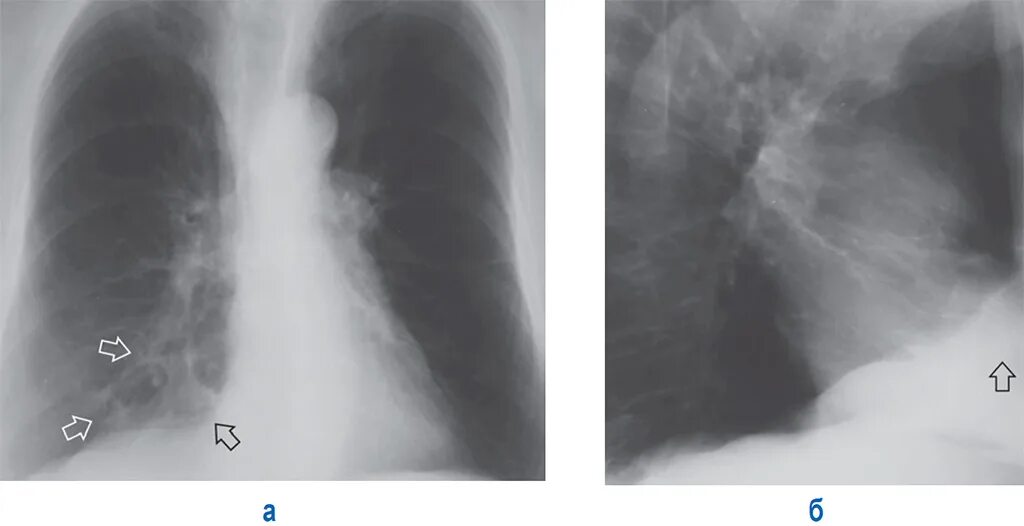

Пневмосклероз рентгенограмма